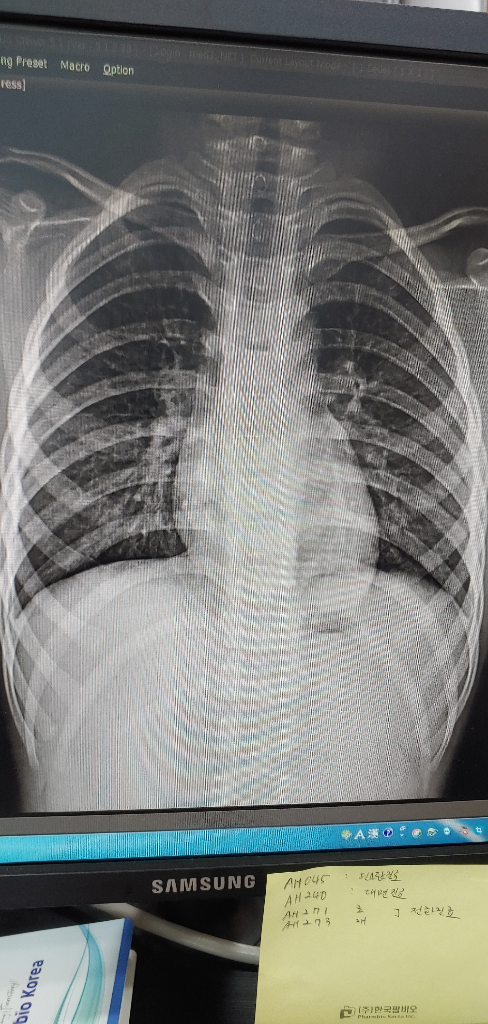

5세 아이 가래가 심해요 엑스레이상 큰 문제는 없다고 합니다.

현재 기침 시럽과 항생제를 복용중인데도 크게 나아지질 않는 것 같아 엑스레이를 찍어보았는데 큰 이상은 없다고 합니다

• 1번 째 사진